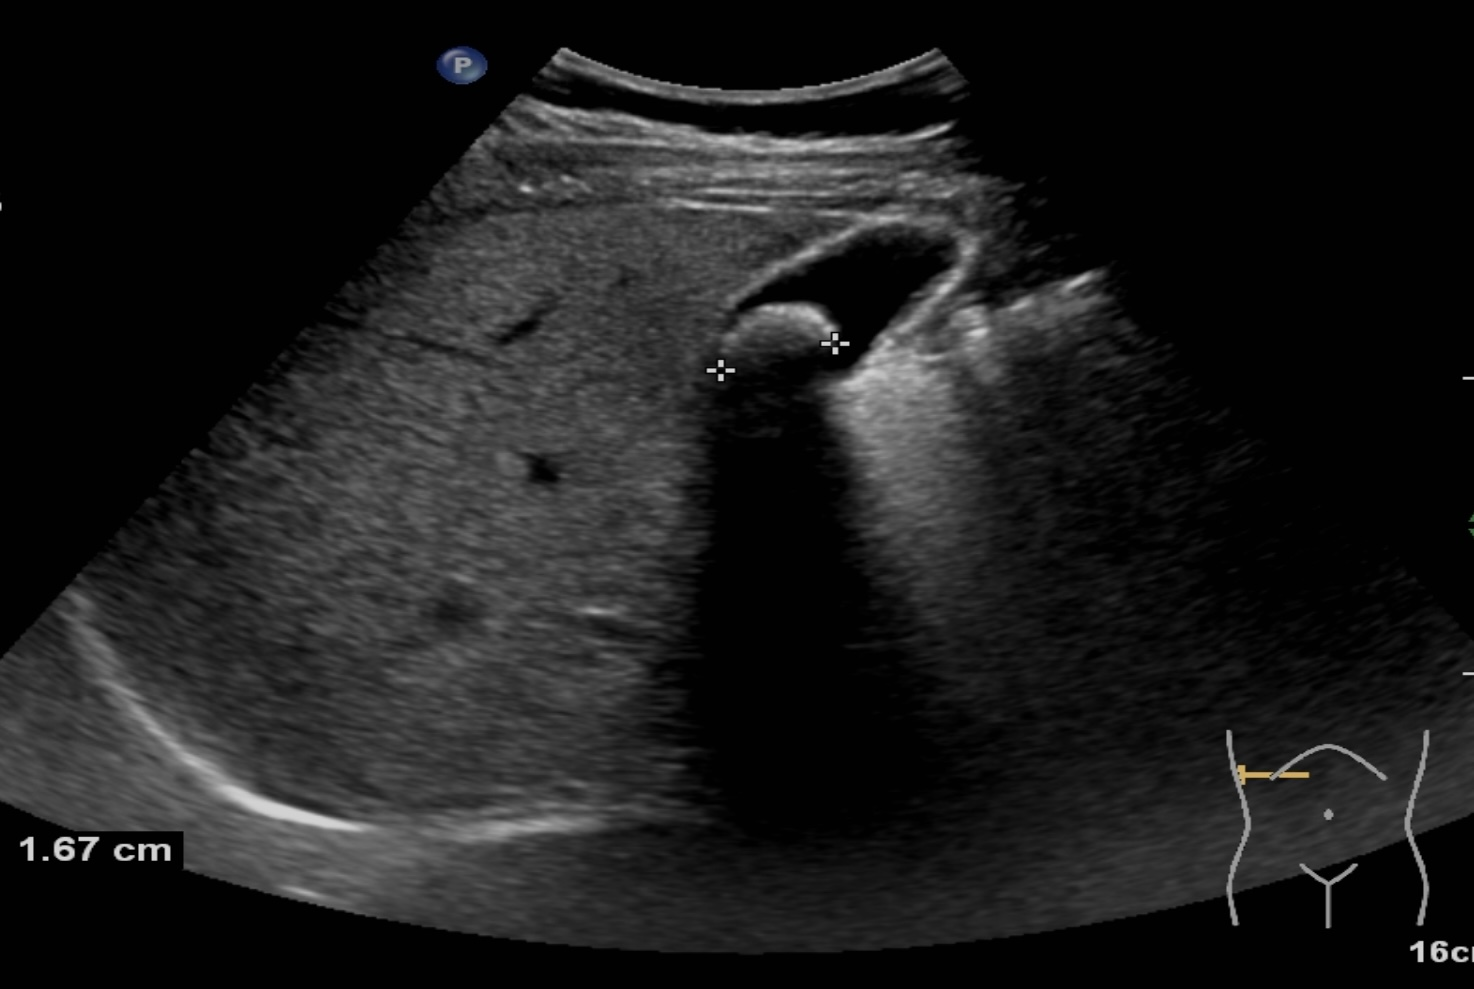

膽結(jié)石診斷方式很多,包括彩超、CT、核磁共振、膽管造影等方式都可以對(duì)膽道結(jié)石進(jìn)行診斷,但是彩超具有無(wú)創(chuàng)、無(wú)痛、無(wú)輻射、廉價(jià)、快速、可重復(fù)性強(qiáng)等優(yōu)點(diǎn),在臨床上被廣泛應(yīng)用作為膽結(jié)石的首選診斷方式。注意做肝膽彩超檢查必須要空腹,才能準(zhǔn)確檢查出膽道結(jié)石哦!

膽囊結(jié)石超聲圖像 | |